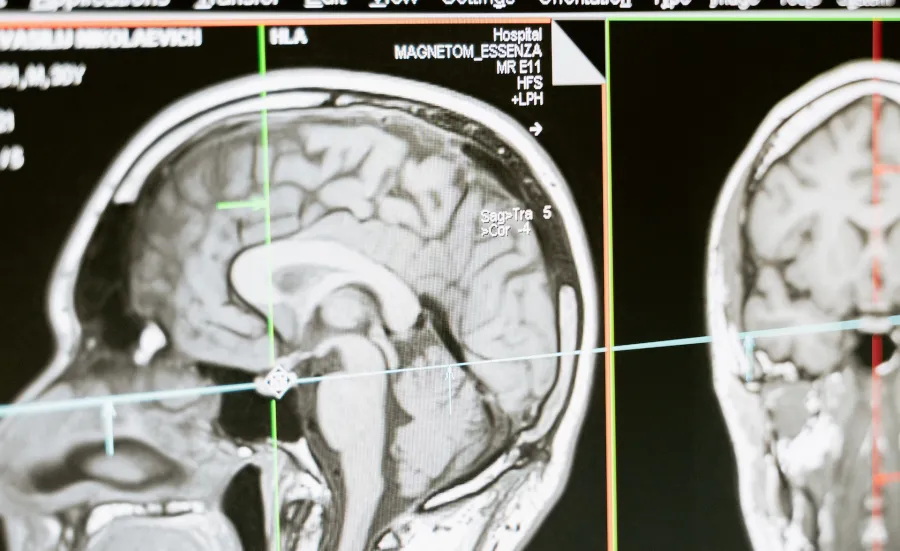

MRI scan of a human head showing the brain in profile

As the brain is enclosed in the skull and inaccessible the tools that we need to use must be advanced, multiple and from different disciplines including mathematics, physics and engineering. This is why IDeAC is leading the way internationally for uncovering the causes of the disease, ways of preventing it and exciting new avenues for treating dementias.